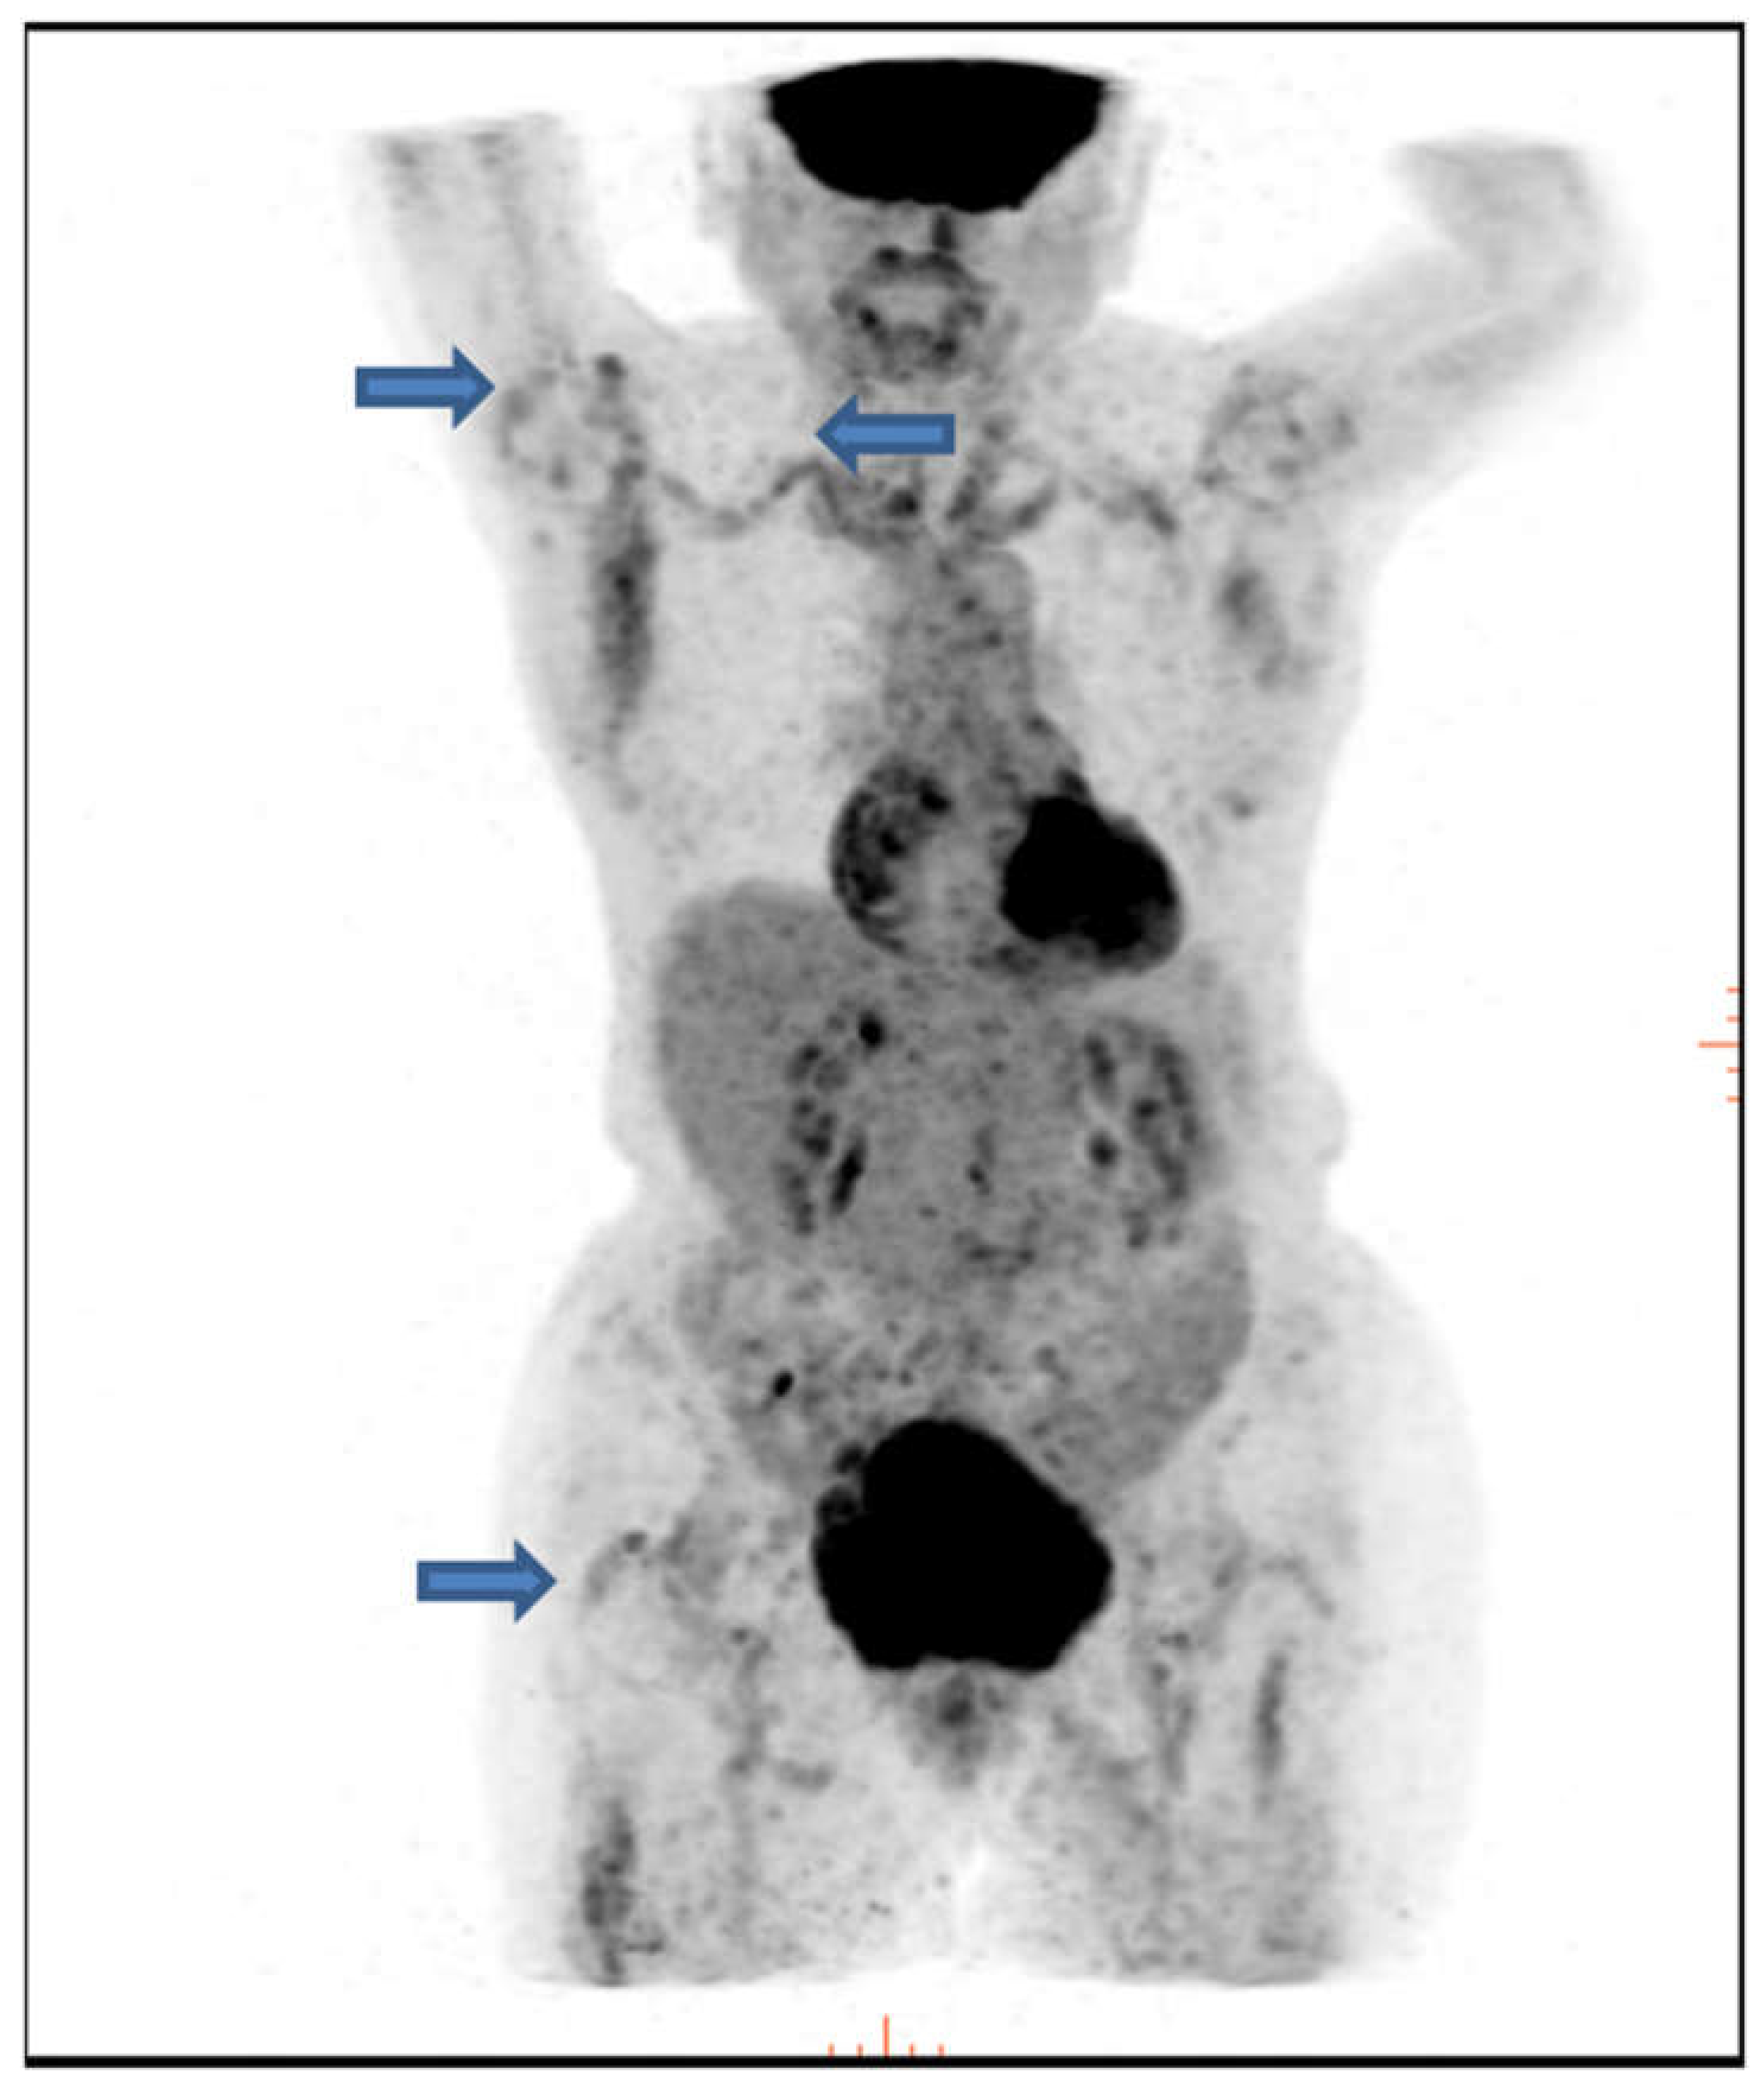

- Yuge, S.; Nakatani, K.; Yoshino, K.; Koyama, T. Diagnosing polymyalgia rheumatica on 18F-FDG PET/CT: Typical uptake patterns. Ann. Nucl. Med. 2018, 32, 573–577. [Google Scholar] [CrossRef]

- Owen, C.E.; Poon, A.M.T.; Liu, B.; Liew, D.F.L.; Yap, L.P.; Yang, V.; et al. Characterising polymyalgia rheumatica on whole-body 18F-FDG PET/CT: An atlas. Rheumatol. Adv. Pract. 2024, 8, rkae003. [Google Scholar] [CrossRef]

- Yamashita, H.; Kubota, K.; Takahashi, Y.; Minaminoto, R.; Morooka, M.; Ito, K.; Kano, T.; Kaneko, H.; Takashima, H.; Mimoiri, A. Whole-body fluorodeoxyglucose positron emission tomography/computed tomography in patients with active polymyalgia rheumatica: Evidence for distinctive bursitis and large-vessel vasculitis. Mod. Rheumatol. 2011, 22, 705–711. [Google Scholar] [CrossRef]

- Rehak, Z.; Sprlakova-Pukova, A.; Kazda, T.; Fojtik, Z.; Vargova, L.; Nemec, P. 18F-FDG PET/CT in polymyalgia rheumatica—A pictorial review. Br. J. Radiol. 2017, 90, 20170198. [Google Scholar] [CrossRef]